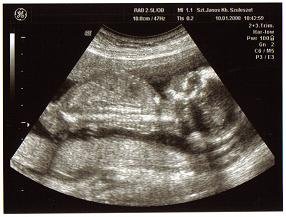

Az uh nagyon jó volt, mindenkinek csak ajánlani tudom a 4D Genesis-t !!!!!!! A szonográfus imádnivaló, laza, jófej, amilyennek lennie kell egy ilyen helyen... :) A csajszink szégyenlős, mert az első fél órában az arcából semmit nem mutatott igazán, belefúrta a méhlepénybe a kis orrát is, nehogy lássuk, milyen krumpli :lol: de tényleg le a kalappal a szonográfus előtt, mert nem azt mondta, hogy jó, hát letelt a fél óra, ennyi a vizsgálat, hanem addig piszkálta, meg hastáncot jártam, hogy csak befordult annyira, hogy lássuk a pofiját... :) végül több, mint egy órát voltunk ott és ugyanannyit fizettünk, mintha fél óra lett volna! :) Súlyunk 860 gramm :shock: úgyhogy ismételten megcáfolom a pocakméret-babaméret dolgot!!!!! Még a csaj is nézett, hogy hogyan fér egy ekkora gyerek ebbe a hasba (hasba? ez has???) :lol:

Ja, és a lényeg.... ismét Zsófi :) 4D-ben is láttam a puncit!!! :)

Elirtam a súlyát... :oops: 880 gramm....